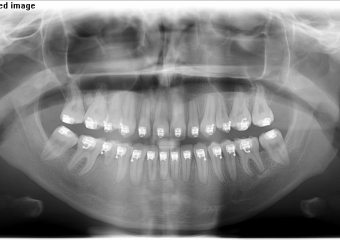

Rx Panorâmico inicial

Rx Panorâmico após a cirurgia 2018